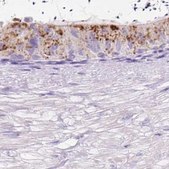

HPA055409

Anti-HEXB antibody produced in rabbit

IHC

immunohistochemistry: 1:50- 1:200

All Prestige Antibodies Powered by Atlas Antibodies are developed and validated by the Human Protein Atlas (HPA) project and as a result, are supported by the most extensive characterization in the industry.

The Human Protein Atlas project can be subdivided into three efforts: Human Tissue Atlas, Cancer Atlas, and Human Cell Atlas. The antibodies that have been generated in support of the Tissue and Cancer Atlas projects have been tested by immunohistochemistry against hundreds of normal and disease tissues and through the recent efforts of the Human Cell Atlas project, many have been characterized by immunofluorescence to map the human proteome not only at the tissue level but now at the subcellular level. These images and the collection of this vast data set can be viewed on the Human Protein Atlas (HPA) site by clicking on the Image Gallery link. We also provide Prestige Antibodies® protocols and other useful information.

• IHC tissue array of 44 normal human tissues and 20 of the most common cancer type tissues.